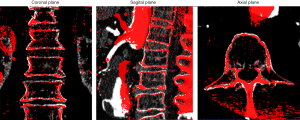

Image registration: Image registration of the CTA with the ceCBCT was based on the bone landmarks of the vertebrae in the open-source programme ITK-SNAP 3.6.0 (9) as shown in Figure 1. First, the ceCBCT dataset was scaled to match the spatial resolution of the CTA dataset, using an automated function of the software, after which rigid transformation (rotation and translation) was used to align the ceCBCT dataset with the CTA dataset.

Correct registration of the bone landmarks is a crucial requirement for the measurement in this study. Whenever image registration failed (inability to align all vertebrae correctly) the patients were excluded from the study.